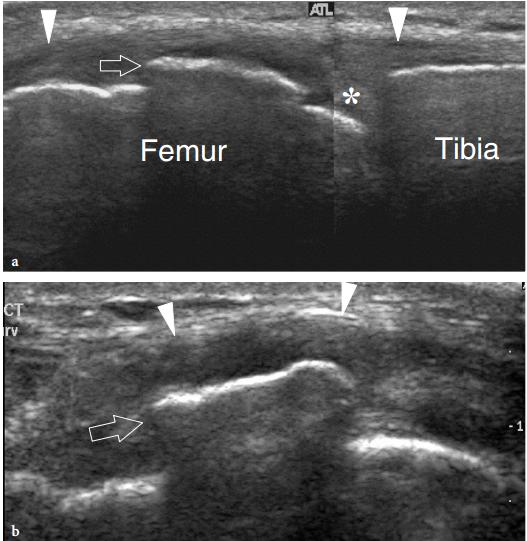

实心剪头所指肌腱附着处增厚。空心三角指内侧副韧带处少量积液